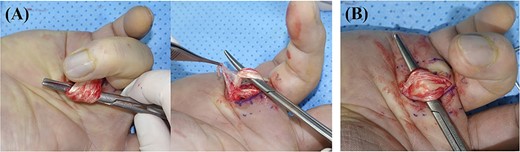

During the operation, the 1.5 cm-sized mass was excised through the longitudinal incision on A1 pulley area. This mass was well defined and encapsulated, and it was tightly attached to the A1 pulley (Fig. 2). There was severe tenosynovitis around flexor tendon and severe adhesion between flexor digitorum superficialis and profundus. Extensive tenosynovectomy around and between flexors was performed. Flexor tendon had a severe splitting lesion (Fig. 3). We considered the possibility of tuberculosis tenosynovitis and performed mycobacterial culture and biopsy. However, histological examination revealed a simple benign fibrous nodule, and there was no evidence of tuberculosis infection.

(A) Severe inflammatory tenosynovitis and adhesion around the flexor tendon was observed; (B) A longitudinally split flexor superficialis tendon lesion with tenosynovitis was observed.